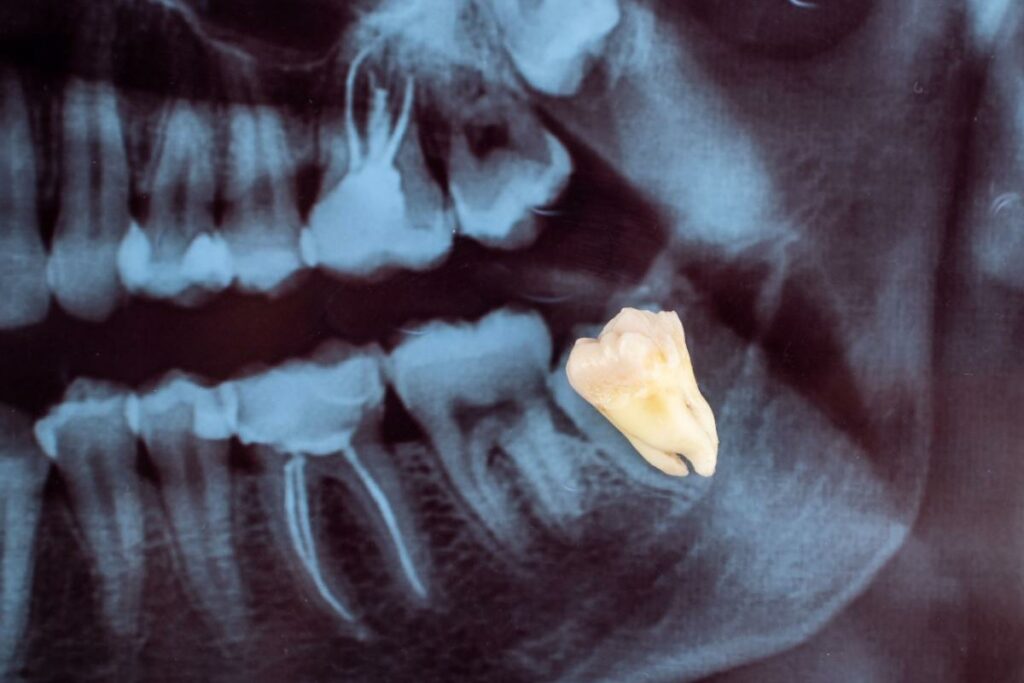

X-rays reveal the position of your wisdom teeth and how their roots are developing beneath your gums. These images help your Ottawa dentist see potential problems before they cause pain or damage to other teeth. Dental x-ray frequency depends on your individual risk factors and oral health needs.